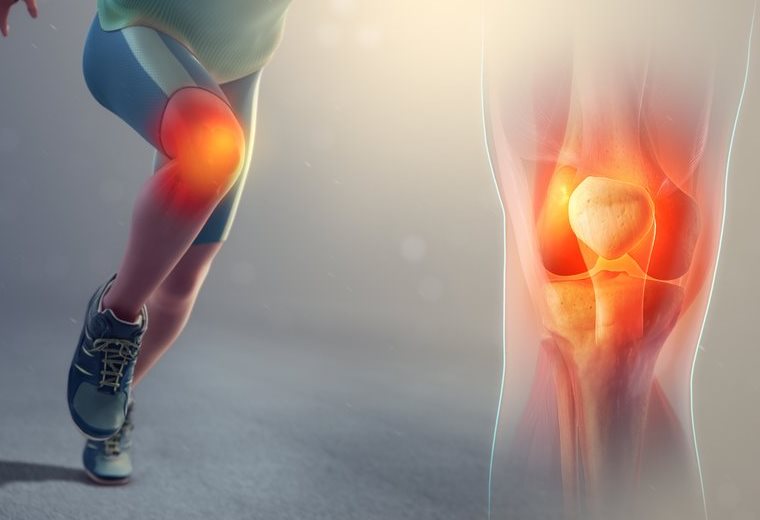

Genunchiul are o stabilitate complexă ce permite alergarea, urcatul scărilor, săritura peste o groapă. Atunci cand apar modificari la nivelul anatomiei genunchiului, echilibrul nostru este compromis.

Traumatismele genunchiului